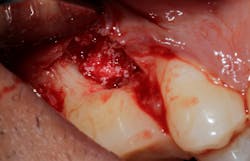

Saving compromised multirooted teeth with root amputation can often be successful, but the technique is sensitive and complex. Proper case selection is essential, and considerations include the following:

There is sufficient bone support around the remaining roots (at least 50% or more is needed) along with sufficient coronal tooth structure (figure 3).How does root amputation compare with other surgical procedures?